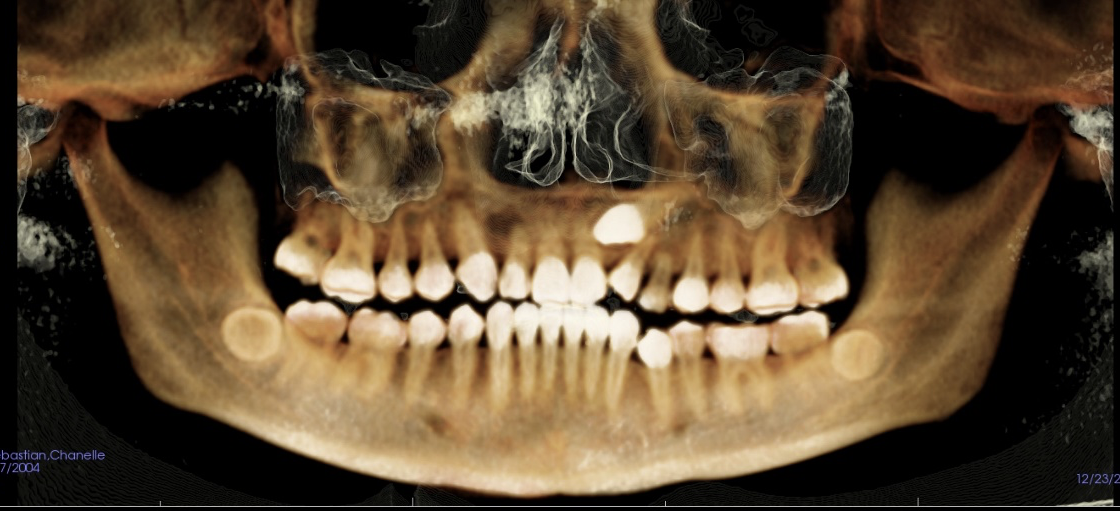

Meet Felix the iCAT! This the name of our 3D X-ray machine. At Buena Vista Orthodontics, we utilize state-of-the-art iCAT 3D imaging technology to provide comprehensive diagnostic capabilities. Nothing hides from us. In 3D, we could capture detailed images of your This advanced cone beam CT teeth, bone, TMJ, airways and much more, giving us a superior diagnostic capabilities.

Why iCAT 3D Imaging? Just look and see for yourself!

The iCAT system visualizes areas that traditional X-rays cannot show, including tooth roots, bone density, airway passages, and TMJ structures. This enhanced imaging enables us to create more accurate treatment plans and identify potential complications early.